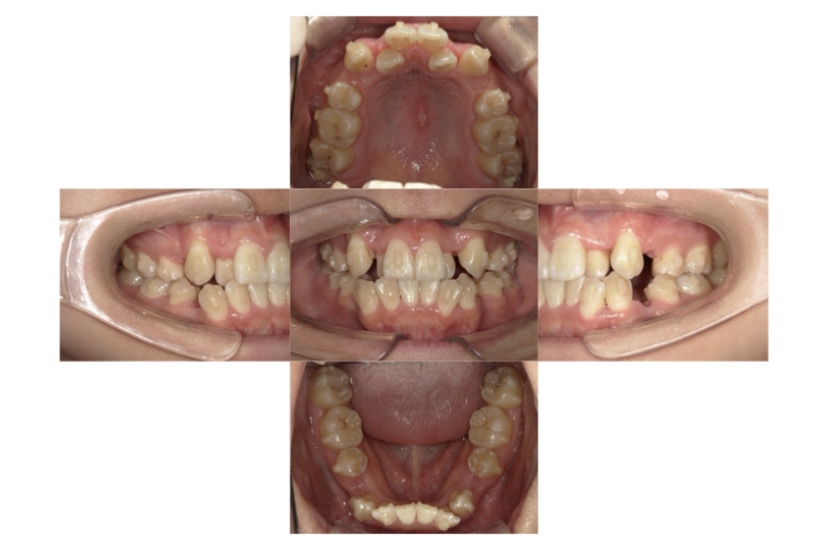

症例1

上顎前突、叢生

抜歯

ブラケット矯正

上下顎叢生、上顎前突(出っ歯、上下の前歯のガタガタ)のケースです。

装置はラビアル(上下表側)で、上顎の小臼歯を2本抜歯を行っています。抜歯したスペースを使って、上の前歯の後方移動と叢生(ガタガタ)と出っ歯の改善を行っています。下は歯と歯の間にIPR(隣接面削合)を行い、スペースを確保し、叢生の改善を行っています。

主訴 前歯のガタガタと出っ歯が気になる。

年齢・性別 47歳 女性

お住まいの地域 神奈川県川崎市

治療方針 抜歯スペースおよびIPRを利用して上前歯の叢生(ガタガタ)の改善

抜歯部位 上顎左右第一小臼歯

使用装置 ラビアル(上下表側)、顎間ゴム

治療期間 2年0か月

治療回数 15回

リテーナー クリアリテーナー

BEFORE